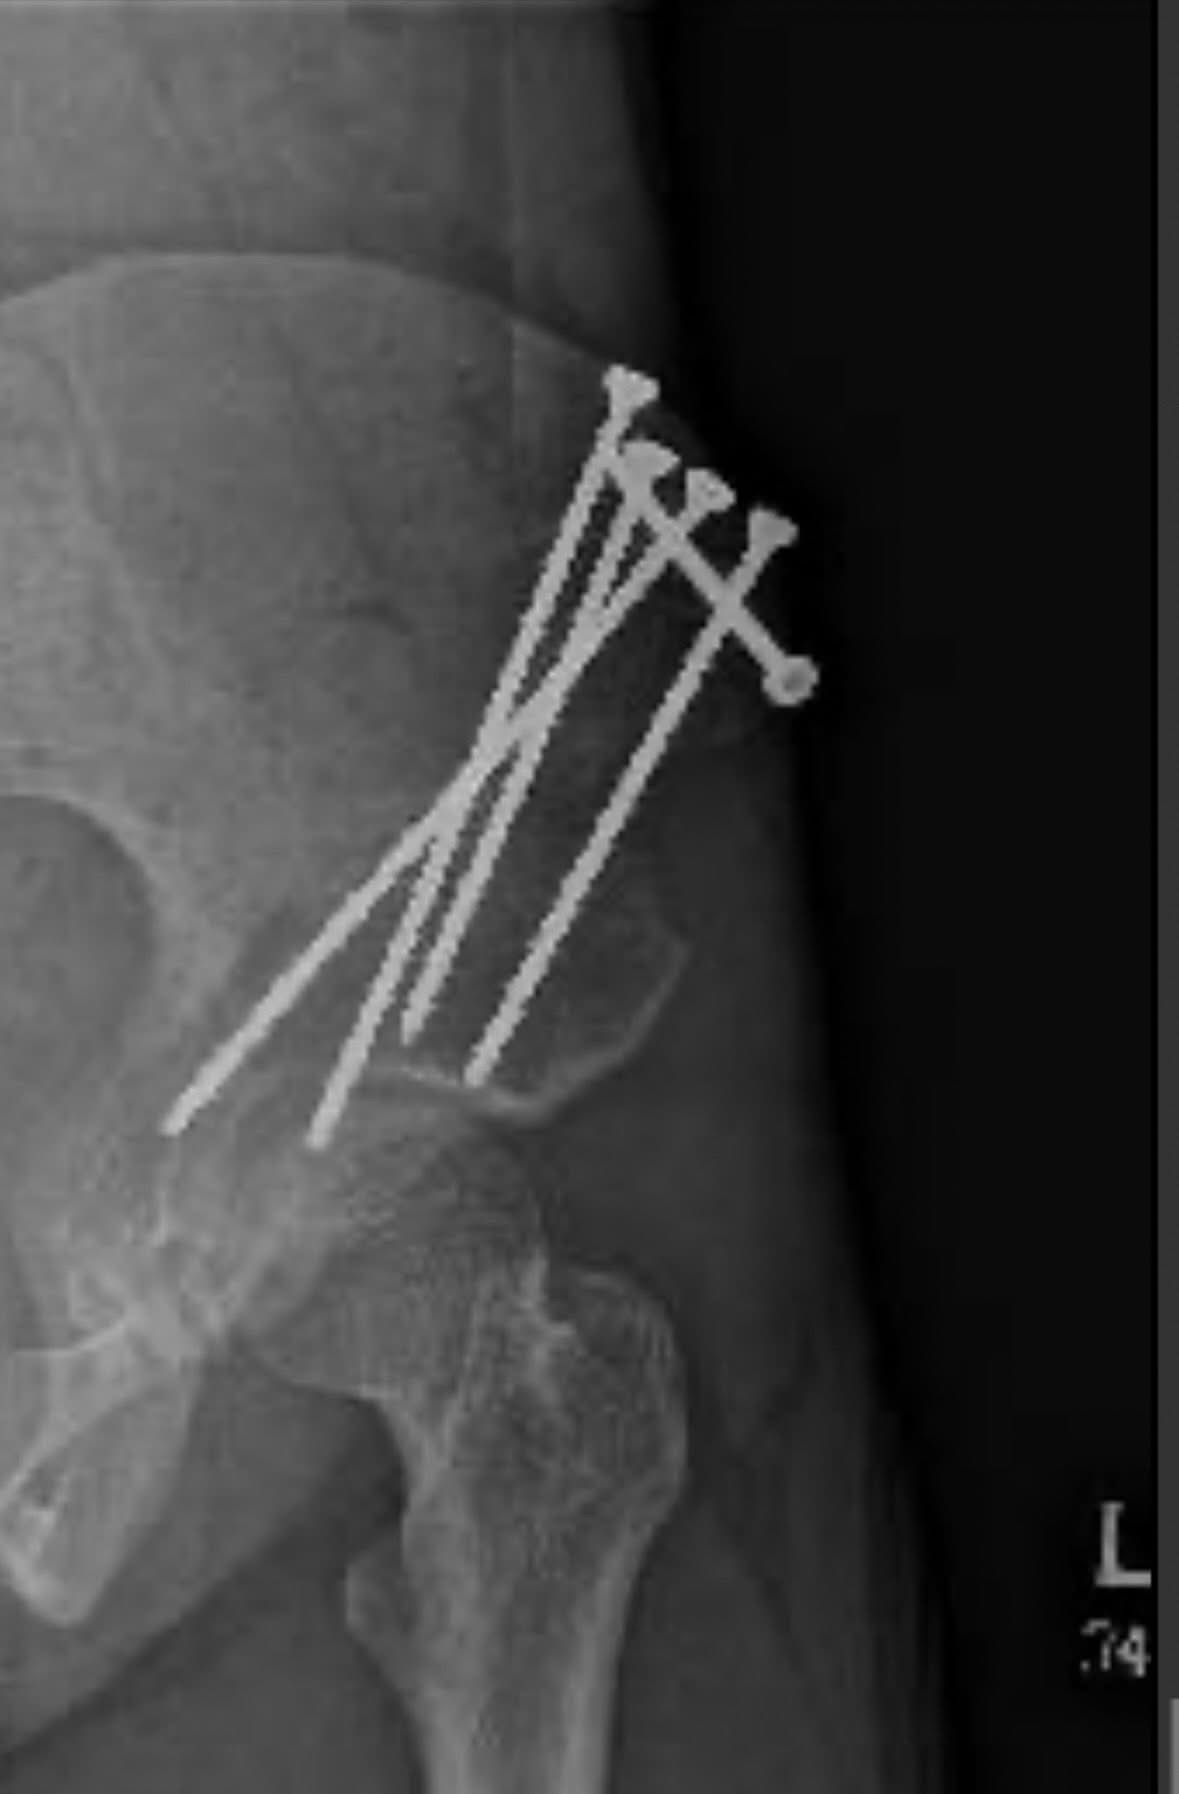

Right now, I’m preparing for a pretty major surgery called a periacetabular osteotomy (PAO). A PAO is a hip surgery that involves a surgeon making multiple cuts into the pelvis and repositioning a section of it to correct hip dysplasia. This is the next step in a series of surgeries I plan to have completed before I age out of my health insurance.

For a little insight into my medical conditions, I have a collection of different diagnoses that go hand in hand with each other (aka comorbidities). I have Ehlers-Danlos syndrome (EDS), which ultimately most of my diagnoses, if not all, are related to. I also have Postural Orthostatic Tachycardia Syndrome (POTS), Mast Cell Activation Syndrome (MCAS), Chiari Malformation, Tethered Cord Malformation, Hip Dysplasia, as well as other diagnoses. EDS is a connective tissue disorder that can impact many different functions of the human body. For most of my life, there has been very little awareness of these disorders. However, great strides have been made over the last 5-10 years, especially relating to EDS and POTS. Some incredible people have spoken about their experience with Ehlers-Danlos and have used their platforms to spread awareness in the process. For example, Rebecca Yarros, a New York Times bestselling author, also has EDS and POTS, and created the Empyrean book series that features a heroine with the same diagnoses. This has led to countless people finding validation, receiving their own diagnoses, being filled with hope, as well as triggering a massive wave of awareness. I am eternally grateful to Rebecca Yarros for showing the world that “not all strength is physical.”